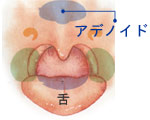

アデノイド

鼻で呼吸がしにくく、口で呼吸をすることが多くなります。

いびきや滲出性中耳炎の原因になることがあります。